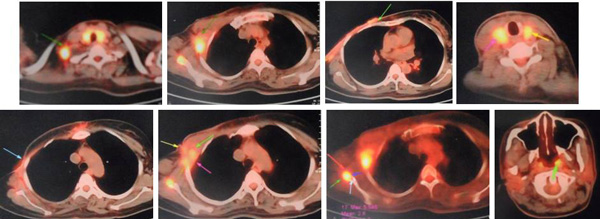

In June to August 2011, KT went to China for treatment. PET/CT scan showed the wound was 14 x 12 cm and the cancer had spread to her lymph nodes, lungs and bone. This was a Stage 4 cancer.

- Patient received iodine seeds implantation and cryosurgery in the lung,

- Iodine seeds implantation in the axillary fossa metastatic lymph nodes.

27 September 2011: Patient received iodine seeds implantation in the scapular region and left costal bone.